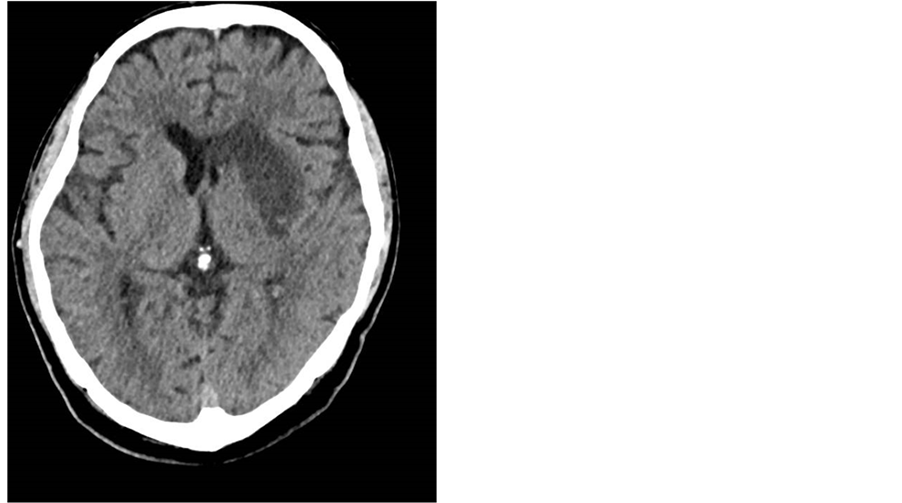

A 53-year-old man with a history of cardiomyopathy of unclear etiology, presented with acute onset right arm weakness and expressive aphasia. He received IV TPA and underwent intra-arterial clot retrieval from the left MCA (middle cerebral artery). Due to his known low EF of 15% - 20% and history of congestive heart failure (CHF), milrinone was started. On the following day he developed atrial fibrillation, with rapid ventricular response (RVR) up to 150 BPM, and hypotension. The patient was anticoagulated, phenylehrine was replaced by neosynephrine and cardizem drip was started. His milrinone drip was discontinued, which resulted in the stabilization of his tachycardia and hypotension. The patient was eventually able to be weaned off all pressors as well as the cardizem drip. His neurological condition improved, and he was discharged to an acute rehabilitation facility [Figure 4].

Figure 4. Head CT showing subacute left MCA ischemic CVA.